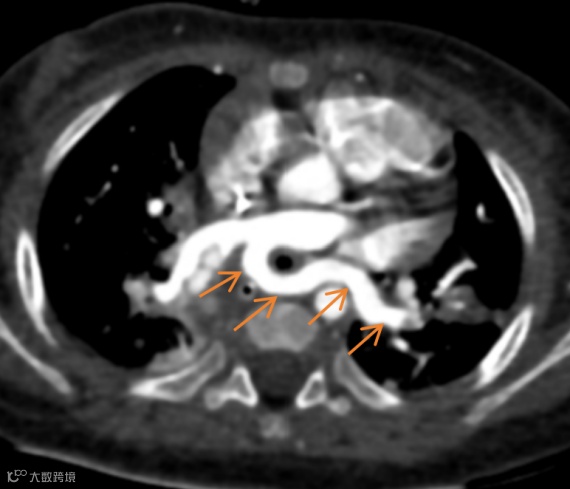

患儿,女,5月龄,喘鸣和反复胸部感染。

胸部CT增强图像如下:

左肺动脉起源异常,由右肺动脉发出,在气管隆突上方与食管之间形成不完整的环状结构。双肺散在分布多发实变影。

左肺动脉吊带,伴双肺感染